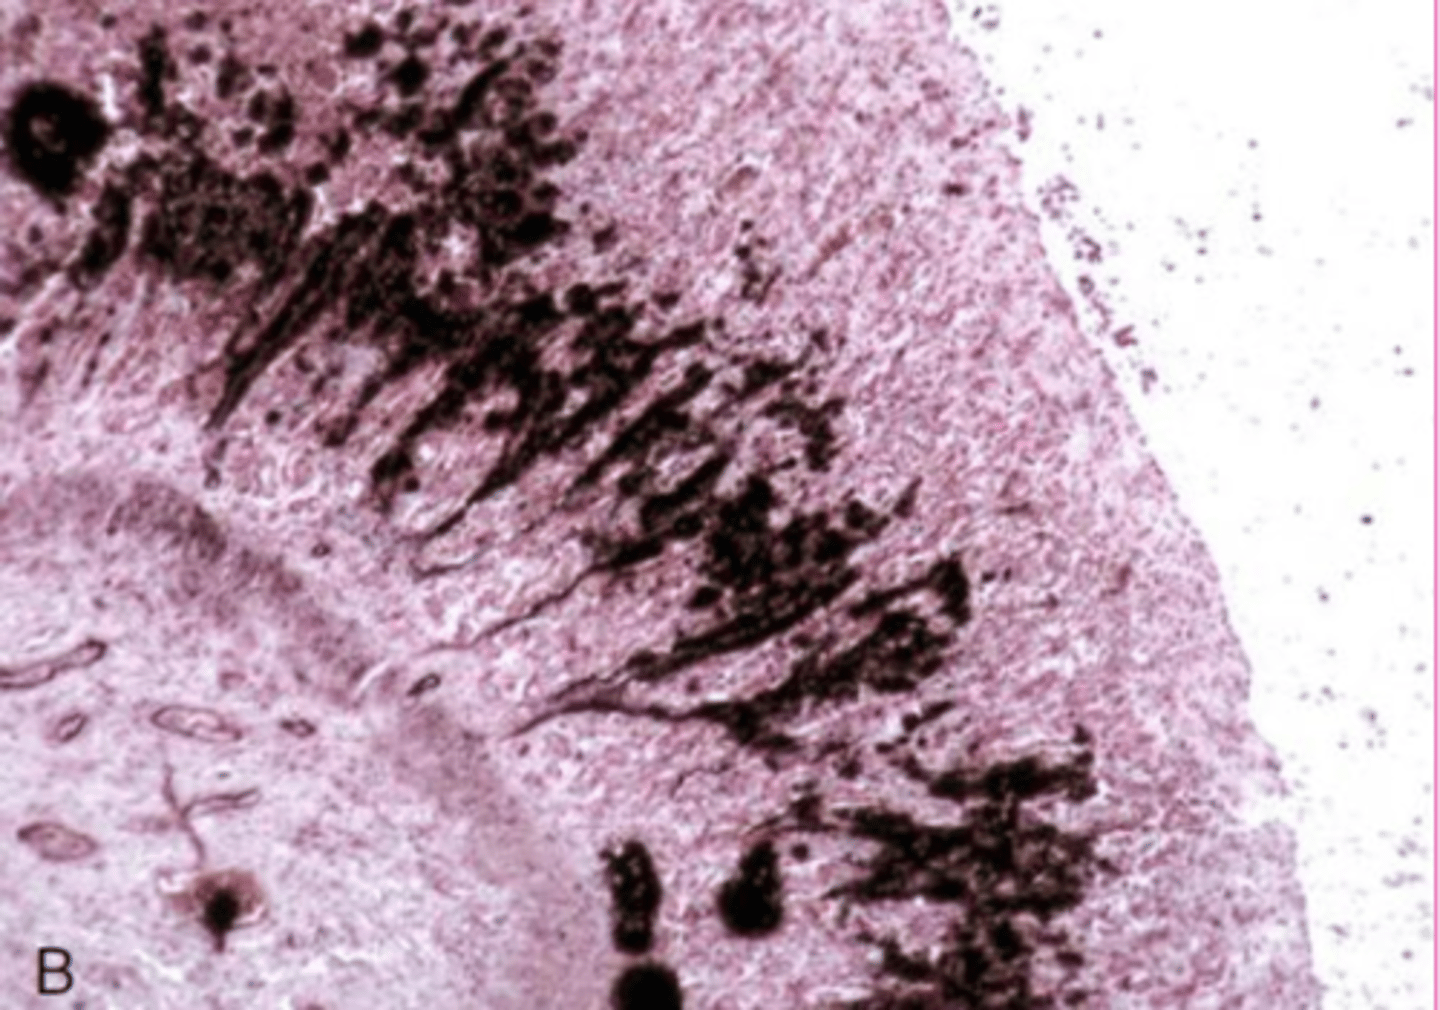

Dural ossification

What is this extracellular accumulation of the dura mater?